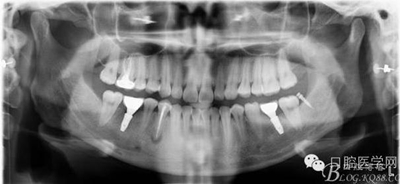

X線片